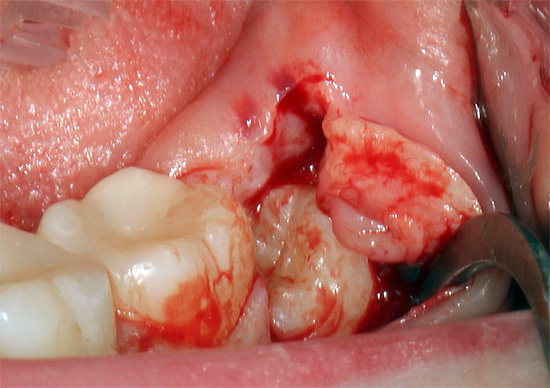

Cosa fare se un dente del giudizio fa male e la gomma si gonfia vicino ad esso?

Se il dente del giudizio è difficile da denti, c'è un forte dolore alle gengive (sotto il cosiddetto cappuccio gengivale), che può diffondersi alla mascella, alla guancia, alla gola, all'orecchio. Il risciacquo domiciliare può alleviare questo dolore solo per un po ', ma non risolve il problema, quindi è necessario andare in clinica: il chirurgo maxillo-facciale o il dentista di solito viene in soccorso.

Studi moderni hanno dimostrato che l'escissione del cappuccio gengivale porta solo un benessere temporaneo e può portare a gravi complicazioni (flemmone, sepsi), fino alla morte. L'unico modo per prevenire qualsiasi rischio e salvare una persona dal dolore è rimuovere il dente del giudizio problematico.

Come accennato in precedenza, la difficile eruzione del dente del giudizio (pericoronite) è la prima indicazione per l'estrazione del dente secondo il moderno approccio alla salute dentale. Certo, puoi sempre convincere il medico a farti solo una sezione del cappuccio gengivale, ma dov'è la garanzia che il dente "non si arrampichi storto", le sue radici non si intrecciano con le radici dei denti vicini, che il cappuccio non ricresce e l'infiammazione non continua di nuovo.

I processi purulenti pronunciati periostite, osteomielite, ascessi, flemmone e altri odontogeni (dal dente) spesso determinano le indicazioni per la rimozione. Se il dente si trova vicino alle radici infiammate o nel seno mascellare stesso, è quasi sempre una questione di rimuovere il dente per interrompere l'alimentazione del seno con l'infezione.